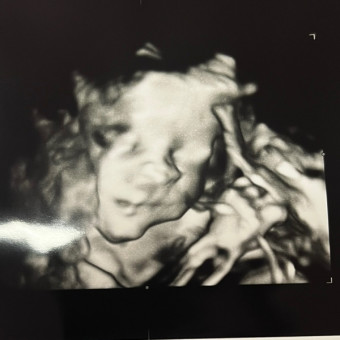

Thank you for visiting our registry! We cannot wait for you to meet our little girl 🩷